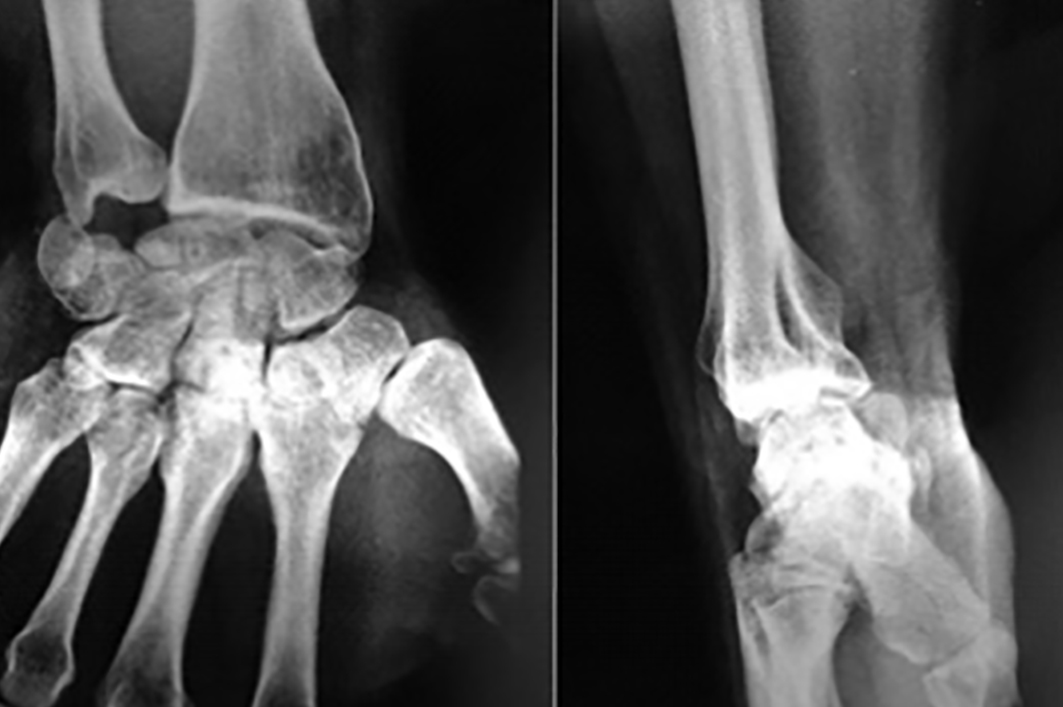

Paciente de sexo masculino, de 26 años, diestro, sin antecedentes personales a destacar, que fue embestido por automóvil mientras manejaba su moto. El paciente presentó una lesión encefálica focal que requirió tratamiento médico. Estuvo en coma 20 días, aparentemente sin otras lesiones. Luego, ya con vida de relación retomada, el paciente relató dolor e impotencia funcional de su mano derecha. Tumefacción y dolor a la movilización (pasiva-activa) y a la prehensión en el examen físico. Las radiografías y el TC mostraron una luxación volar de hueso grande de mano derecha (Figura 1) asociada a fracturas de la base del tercer metacarpiano y de hueso piramidal, ambas sin desplazamiento (Figura 2). A las 8 horas de establecer el diagnóstico se realizó una reducción abierta por vía palmar con fijación interna, con alambres de Kirchner de 1,5 mm, (Figura 3). Se agregó un mini fijador externo para proteger la estabilidad de la osteosíntesis del carpo y manejar las partes blandas lesionadas. No se realizó reconstrucción ligamentaria.

Se extrajeron los alambres y el fijador externo a las 6 semanas. El paciente empezó con ejercicios activos y pasivos de recuperación del rango de movimiento de mano y puño. A los 12 meses el paciente no mostraba dolor, a pesar de que ya se visualizaban cambios radiográficos con osteocondensación del hueso grande, pero sin colapso carpiano (Figura 4).

En cuanto a la movilidad a los 6 años, encontramos una mayor pérdida de la flexión del puño, comparada con la extensión. Pensamos que esto se deba a la pérdida del componente de flexión de que se observa entre la primera y segunda fila del carpo normalmente y que corresponde aproximadamente a 35° de flexión de puño (7). Por último, no encontramos clínica de dolor espontáneo y tampoco relacionada con la práctica de deporte de contacto, a pesar de la osteocondensación radiográfica evidente al año y que muestra cambios radiológicos significativos con un colapso capito-semilunar a los 6 años de seguimiento (Figura 5). Esto guarda relación con las limitaciones observadas clínicamente.